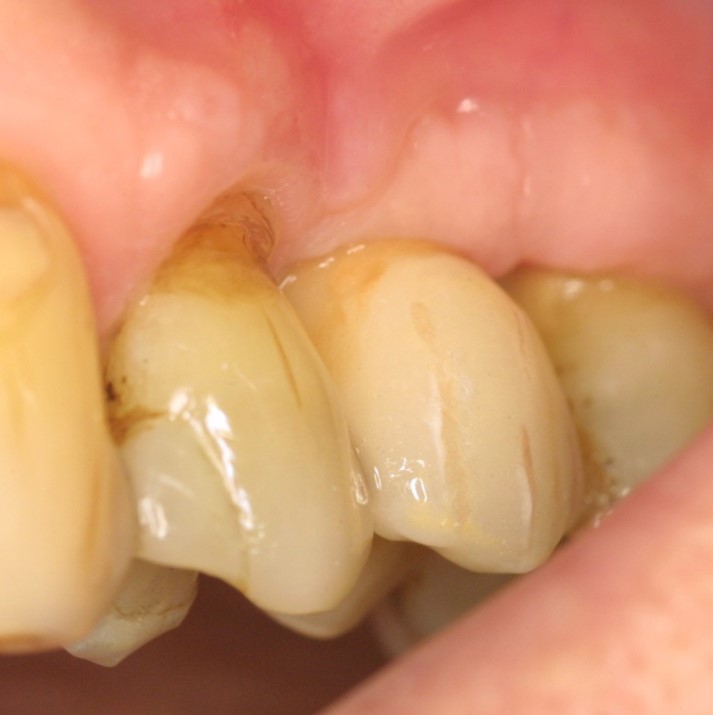

Intrabony defect treated using collprotect® membrane & cerabone® (1) - Cosgarea & Sculean

Pre-surgical probing reveals a deep intrabony defect on the distal aspect of the upper canine.